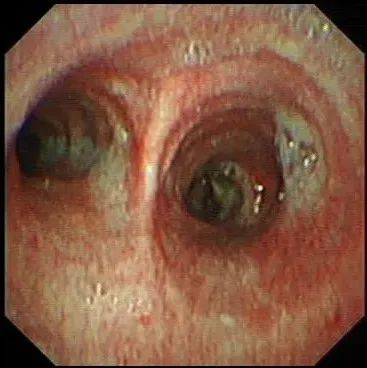

术后复查支气管镜,示右主支气管管腔通畅